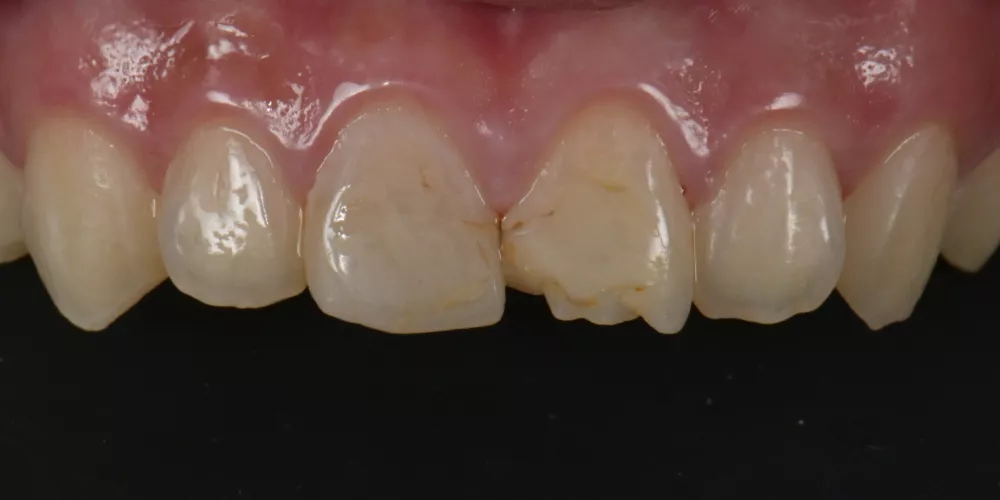

因為我知道,牙齒不只是局部問題,它牽動著一個人的生活全貌。能不能自在吃飯、敢不敢開口笑、在人前是不是有自信,都與牙齒息息相關。

從許多案例發現,長期維持良好牙齒健康的長輩,不僅外表比同齡人年輕,精神狀態、生活品質都明顯更好。因為他們不只能自在的社交,同時也能好好享受食物的美味,這些看似理所當然的日常,其實都建立在一次次用心的治療細節中。